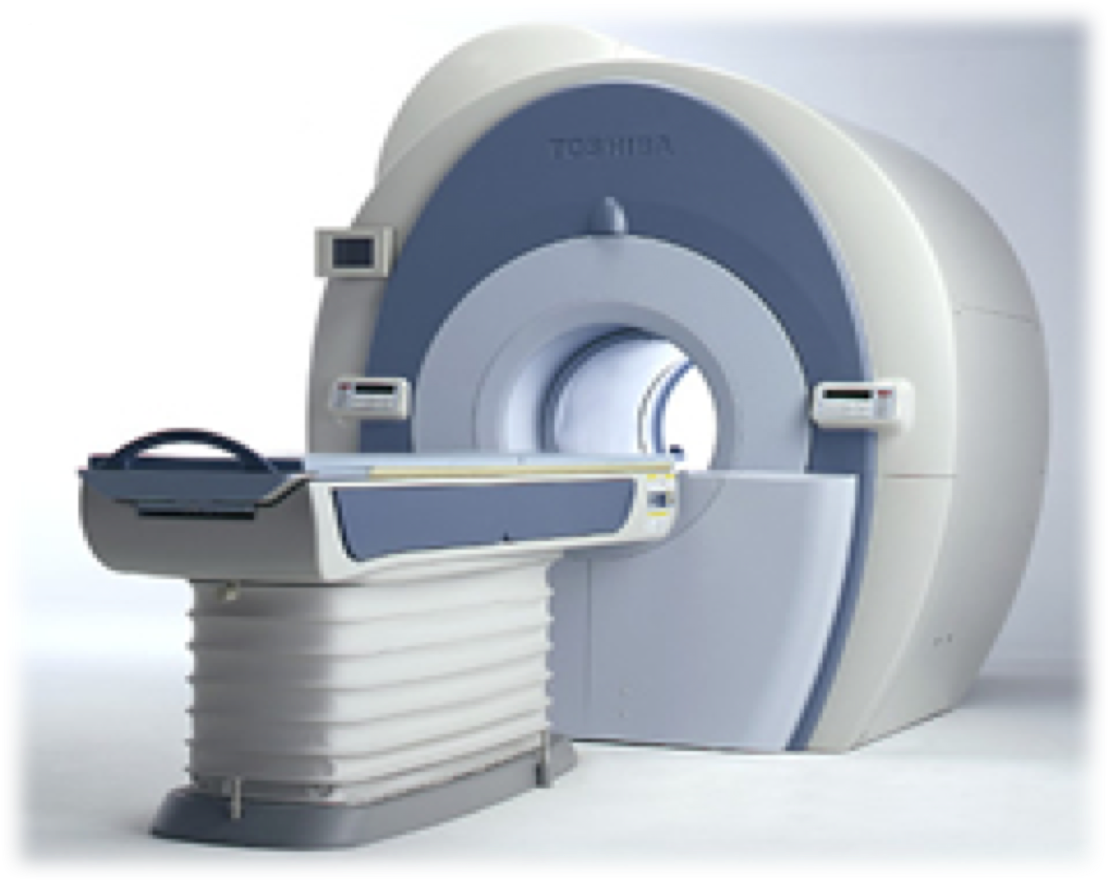

装置の紹介

当院では1.5テスラ キヤノンメディカルシステムズExcelart Vantage (MRT-2003)を用いています。

この装置は撮像時の騒音が従来装置に比べ約90%低減されています。また、検査架台の長軸が短縮され解放的でリラックスして検査を受けることができます。